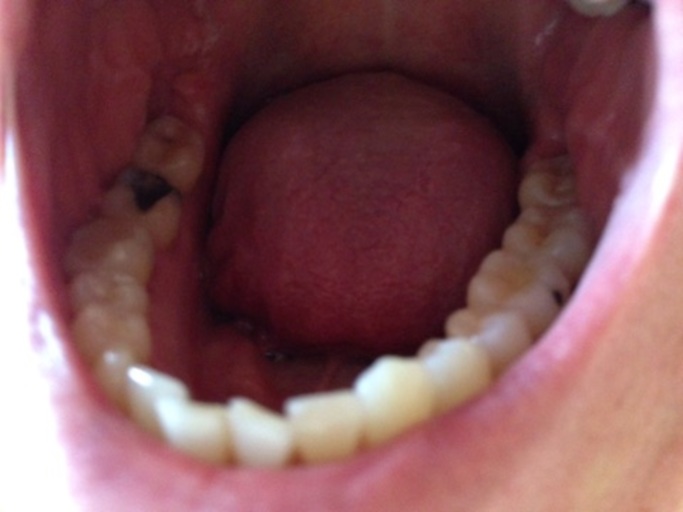

I got a cavity filled a couple months ago and had to go back multiple time to get it sanded down right because it was causing pain. I also had sensitivity in another area and before I went to the dentist I looked at the tooth and in the crevasse was a black spot. I ask the dentist to look he said he didn't see anything but to be safe he did an x ray and said nothing was there. I switched to sensidine tooth paste and the pain went away but the black spot is still there. I guess I'm kind of wondering what the chances of having a cavity there is? and could it be something else?

Usually a tooth that has a cavity appears darker in color.  It could be that there is stain in the deep grooves on the occlusal (chewing) surface of your tooth.  It may not be active caries, but could become a carious lesion in the future. If your dentist has a diagnodent, a laser that detects caries where the instrument cannot fit, the reading will let him/her know the depth of the lesion and if there is demineralization or not.  You can also ask if the dentist can remove the dark spot and place a dental sealant to protect the tooth.  A sealant is a protective coating that will stop debris from staining the surface of your tooth and prevent caries.